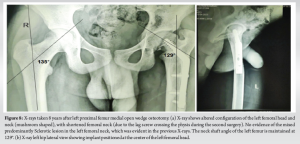

Post-operatively, the patient was mobilized after 6 weeks. Intraoperative biopsy ruled out any tumor/infective foci in the left femoral neck region. The osteotomy healed well. However, 1 year and 9 months after the initial surgery, the patient experienced a recurrence of pain in the left hip and limp. Radiograph showed recurrence of left coxa vara (Fig. 4) with a trans cervical fracture in the neck of the left femur. Probably the tip of the screws inserted into the neck was acting as stress risers. The patient underwent left femur implant removal + medial open wedge osteotomy with bone grafting from the left tibia + internal fixation with pediatric dynamic hip screw (DHS) on May 21, 2015. During the surgery, the lag screw (45 mm) was placed across the physis (stability was prioritized). Post-operatively, the NSA and HE angle were restored (Fig. 5).